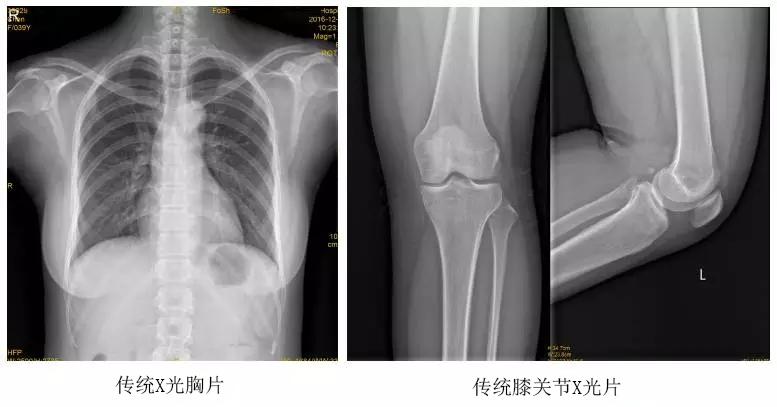

臨床在診治脊柱及下肢畸形時(shí),往往采取矯正手術(shù)治療。這就需要在對(duì)其進(jìn)行手術(shù)前后,拍攝全脊柱或全下肢的X光片作為診治依據(jù),以便分析病情、制定手術(shù)方案和評(píng)估術(shù)后療效。目前大部分醫(yī)院使用的DR攝片機(jī),因拍攝幅面受限,最大規(guī)格43cm,但成人的全脊柱長(zhǎng)度一般約60cm,而全下肢更長(zhǎng),不能一次性拍攝出完整的全脊柱或全下肢的X光影像。以全脊柱攝片為例,各拍攝一張傳統(tǒng)的頸椎、胸椎、腰椎的X片雖然就能觀察到每個(gè)部位局部的側(cè)彎情況,但不能觀察到三者之間的連續(xù)性。因此傳統(tǒng)X光片在這類疾病診斷上存在著一定的缺陷,無法更精準(zhǔn)有效地進(jìn)行臨床診斷和治療。

以某院所攝X光片為例,對(duì)比傳統(tǒng)攝片與全身拼接功能的區(qū)別:

傳統(tǒng)X光片只能觀察每個(gè)部位的局部情況,無法在統(tǒng)一體上進(jìn)行連續(xù)、全面的觀察,全脊柱及下肢全長(zhǎng)片則能直觀的看到整體形變。通過DR全身拼接功能實(shí)現(xiàn)的完整成像,為診治脊柱及下肢畸形提供了完美的臨床影像依據(jù),對(duì)臨床診斷、術(shù)前手術(shù)方案的制定和術(shù)后療效的評(píng)估等臨床應(yīng)用具有十分重要的意義,有效滿足了此類疾病臨床診斷和治療的要求。